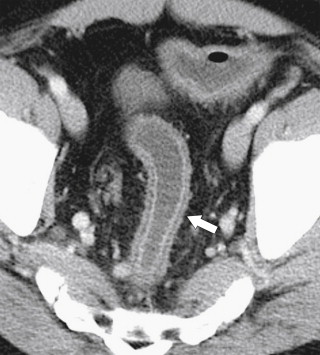

Strongyloides infection can mimic UC in its diffuse form but can also present with focal right colonic disease ( Fig. 5-50 ). Actinomyces infection is usually secondary to pelvic colonization of intrauterine contraceptive devices and may cause a focal, either cecal or rectosigmoid, colitis ( Fig. 5-51 ). Actinomyces may also be associated with right-sided ileocecal infection after secondary infection following appendectomy.

Figure 5-51, BE ( A ) and axial contrast-enhanced CT ( B ) in a 39-year-old woman with pelvic actinomycetes infection with sigmoid wall thickening ( arrow ) and narrowing ( small arrows ) and a pelvic abscess ( arrowhead ).